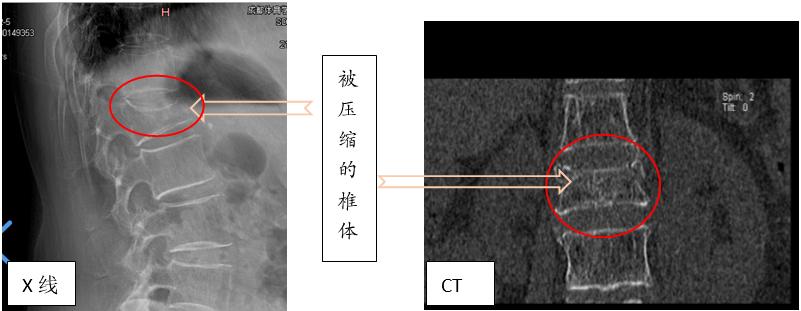

影像学检查

常用的有X线、CT、MRI、骨扫描。